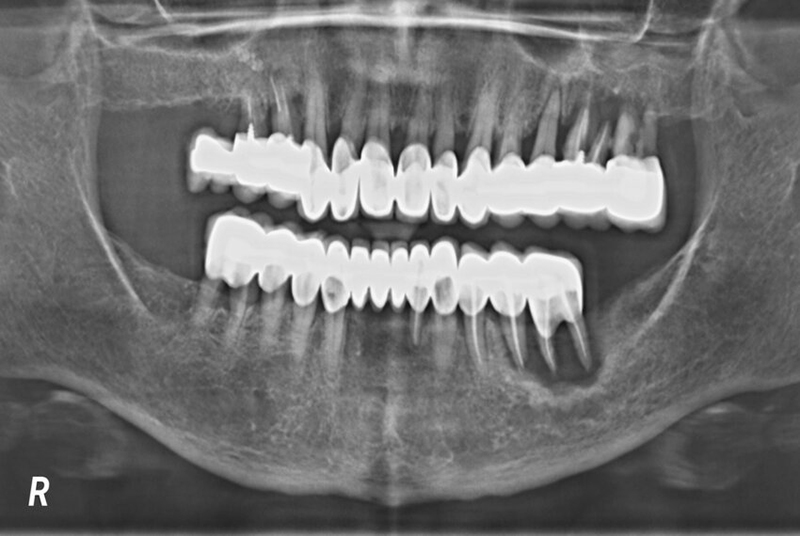

Trước khi tiến hành cấy ghép răng Implant, bác sĩ cần thực hiện các bước thăm khám kỹ lưỡng để đánh giá tình trạng xương hàm, bao gồm việc chụp phim X-quang hoặc sử dụng công nghệ CT Cone Beam để xác định mức độ tiêu xương cấy Implant và kiểm tra mật độ, chiều cao của xương hàm. Nếu xương hàm còn đủ vững chắc, bác sĩ có thể tiến hành cấy ghép Implant trực tiếp.

Công nghệ chụp ảnh X-quang giúp xác định rõ tình trạng xương hàm